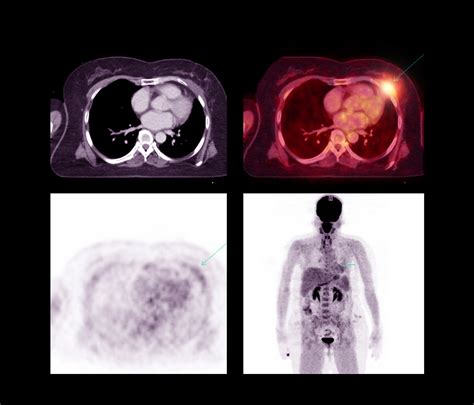

A Pet Scan Image is created by injecting a small amount of radioactive tracer into the body. This tracer emits positrons, which collide with electrons in the body, producing gamma rays. The PET scanner detects these gamma rays and constructs a three-dimensional image of the body's internal activity. The resulting images highlight areas of high metabolic activity, which can indicate the presence of disease.

• Oncology: PET scans are widely used to detect and stage cancer. They help identify cancerous tumors and determine the extent of the disease, aiding in treatment planning.

Interpreting Pet Scan Images requires specialized training and expertise. Radiologists and nuclear medicine physicians analyze the images to identify areas of abnormal metabolic activity. The interpretation process involves:

• Comparing the PET scan images with other imaging modalities, such as CT or MRI scans, to provide a comprehensive view of the body's structures and functions.

• Identifying areas of increased or decreased metabolic activity, which may indicate the presence of disease.

For example, in oncology, areas of high metabolic activity on a Pet Scan Image may indicate the presence of cancerous tumors. In neurology, abnormal patterns of tracer uptake can help diagnose conditions like Alzheimer's disease or epilepsy.

• Hybrid Imaging: Combining PET with other imaging modalities, such as CT or MRI, provides a more comprehensive view of the body's structures and functions. Hybrid imaging systems, like PET/CT and PET/MRI, offer improved diagnostic accuracy and treatment planning.